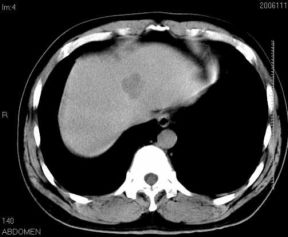

男性,48岁

肝内占位,性质?

肝内多发低密度占位病变,边缘清晰,无强化,肝转移瘤可能

肝内多发低密度占位病变,边缘清晰,无强化,肝转移瘤可能大,请将胃喝水充盈以后再扫描看看,我看大弯侧胃壁较厚。

肝内多发不规则形状低密度灶,强化不明显,考虑转移,积极查找原发灶

患者,男性,48岁

肝内多发低密度类圆形病灶,边缘清晰.增强无强化.

意见:1,考虑多发转移瘤;

2,囊肿与血管瘤不排除.

肝内多发不规则形状低密度灶,强化不明显,考虑转移,找找原发灶

1肝内多发低密度影,考虑:转移瘤 2胃大弯侧胃壁明显增厚,建议胃镜检查除外胃癌

我认为先考虑原发性肝癌。

首先考虑转移瘤。

多考虑转移瘤

转移瘤?